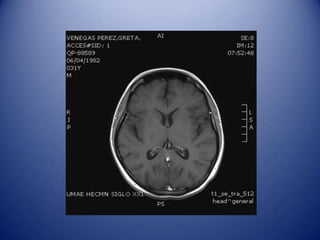

Identifying differential diagnosis

Embolic infarct.

Opportunistic infection.

Brain abscess.

NP SLE.

Brain tumor.

MRI Diagnosis

Radiology: Infarcts (embolus), cortical,

in two different territories, restricted

diffusion, low ADC.

Neurology: Opportunistic infection

(toxoplasmosis) vs. brain abscess

Identifying differential diagnosis Embolicinfarct. Opportunistic infection. Brain abscess. NP SLE. Brain tumor.

• 18.

MRI Diagnosis Radiology: Infarcts(embolus), cortical, in two different territories, restricted diffusion, low ADC. Neurology: Opportunistic infection (toxoplasmosis) vs. brain abscess (headache, fever, seizures).